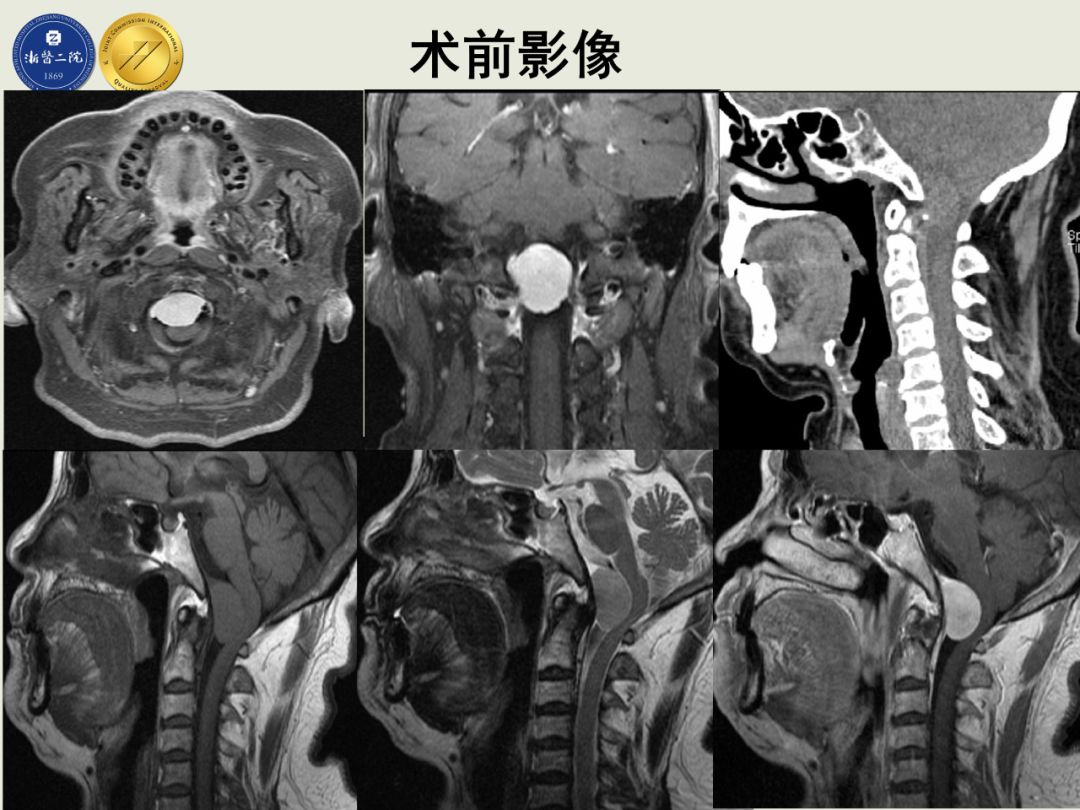

由来自包括北京天坛、上海华山等全国各大医院的十名选手经专家评委网上盲审最终进入总决赛。浙二神经外科在张建民主任安排下,由吴群主任带队,由洪远副主任医师在大会上展示一例高难度神经内镜下经鼻-斜坡-齿状突入路切除腹侧型枕骨大孔区脑膜瘤,凭借创新手术术式、娴熟手术技巧和满意手术疗效,获得大会评委一致认可,最终在总决赛中脱颖而出,获得唯一的特等奖。